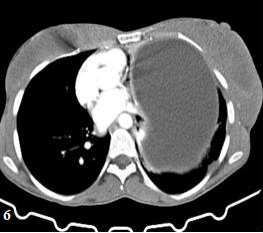

The patient's ECG showed normal sinus rhythm, and her myocardial-specific enzyme levels were within the normal range. A cystic lesion was found to be causing pressure on the left ventricle and atrium on the lateral wall of the pericardium, as revealed by CXR and CT scans. Abdominal ultrasonography and contrast-enhanced CT scans confirmed the presence of a large hydatid cyst lesion with septation in the liver (Figure 6,7,8).

Figure 6: shows a CT scan with a substantial cystic lesion of the left lung, which compressed the heart and mediastinum, carina, and liver cyst.

Figure 7: shows a coronal CT scan of the liver with huge cystic, septation, and laminated membrane.